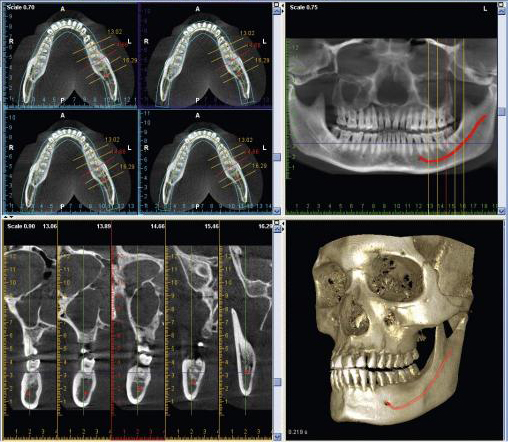

Rentgenologiniai tyrimai yra reikalingi gydymo plano sudarymui prieš implantacijos, sinuso dugno pakėlimo ir kaulo priauginimo, protinių dantų rovimo operacijas, nes pateikia virtualius paciento veido, žandikaulių srities, šaknų skilimų, kaulo lūžių vaizdus. Kompiuterinė tomografija parodo burnos ir aplinkinių audinių trimatį vaizdą (3D), tad ją rekomenduojame daryti pacientams prieš chirurgines procedūras siekiant tiksliai suplanuoti gydymą ir įvertinti kaulo būklę, jo storį, visa tai išanalizuoti trijose plokštumose.

• Greita. Pažangi planavimo ir kompiuterinės tomografijos tyrimų programa turi galimybę suplanuoti visą gydymą, naudojant programoje esančius implantus galima matyti, kaip viskas atrodys po procedūros. Pats kompiuterinės tomografijos skenavimas užtrunka iki 15 sekundžių, tad pacientui net nespėjus sujudėti, burnos ir dantų būklės vaizdas jau būna užfiksuotas.

• Optimalu. Kiekvienu individualiu atveju kompiuterinės tomografijos tipas ir dydis pasirenkamas pagal gydymo planą. Atsižvelgiant į paciento burnos būklę, atliekamas vieno arba dviejų žandikaulių, universalus, vaiko žandikaulio ar aukštos raiškos skenavimas, atitinkamai gaunama nuo 10 cm x 8 cm iki 5 cm x 5 cm išmatavimų nuotrauka. Tinkamiausią kompiuterinės tomografijos dydį Jums parinks Jūsų gydytojas-odontologas, atsižvelgus į Jūsų burnos ir dantų būklę.

• Tikslu. Kompiuterinė tomografija trimačiu vaizdu pateikia aiškesnį 75 mkm vaizdą, kuris naudojamas endodontijoje šaknies kanalų gydymui. Kompiuterinė tomografija suteikia galimybę įvertinti dantų ir jos audinių būklę iš visų pusių, pašalinami visi iškraipymai. Turint tikslius išmatavimus išvengiama netikslumų implantacijos ir kitų chirurginių operacijų metu, nepažeidžiami nervai ir kraujagyslės, sinuso ertmė.

Kompiuterinė tomografija gali būti įrašoma į laikmeną arba saugoma „PAPADENT“ odontologijos klinikoje. 3D žandikaulio nuotrauka Jums suteiks išsamią informaciją apie kaulo būklę, jo tankį, plotį ir aukštį. Atlikus 3D dantų nuotrauką Jums bus sudarytas išsamus gydymo planas, pagal kurį bus atliekamos procedūros. Lyginant su panoramine dantų nuotrauka, kompiuterinė tomografija parodo visą vaizdą 3D formatu, įvertina svarbias anatomines struktūras, suteikia žymiai daugiau informacijos implantacijai ir kitoms procedūroms.

Visų dantų atkūrimas all-on-4 metodika. Implantacija. Šiuo atveju būtina padaryti 3D kompiuterinę tomografiją. Panoraminė rentgeno nuotrauka yra dvimatė, tai yra ji suteikia informaciją tik apie dvi dimencijas – aukštį ir plotį. Įvertinti, ar jūs esate tinkamas kandidatas dantų implantams, reikia matyti ir kaulo tūrį – būtent tai ir parodo KT nuotrauka.

Sinuso dugno pakėlimas ir kaulo augmentacija. Analogiškai kaip ir dantų implantams, norint pakelti sinuso dugną ar priauginti kaulo, reikia matyti ir įvertinti kaulo tūrį, sinuso dugno padėtį.